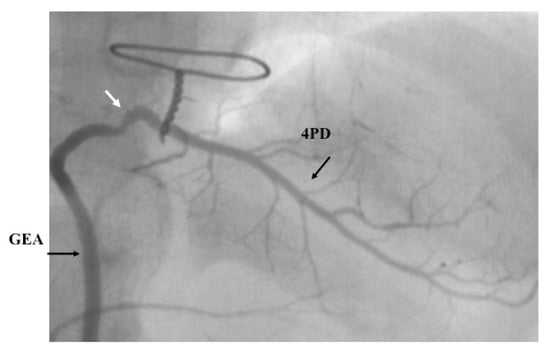

- Tsuda, E.; Fujita, H.; Yagihara, T.; Yamada, O.; Echigo, S.; Kitamura, S. Competition between native flow and graft flow after coronary artery bypass grafting. Impact on indications for coronary artery bypass grafting for localized stenosis with giant aneurysms due to Kawasaki disease. Pediatr. Cardiol. 2008, 29, 266–290. [Google Scholar] [CrossRef]

- Takeuchi, Y.; Gomi, A.; Okamura, Y.; Mon, H.; Nagashima, M. Coronary revascularization in a child with Kawasaki disease: Use of right gastroepiploic artery. Ann. Thorac. Surg. 1990, 50, 294–296. [Google Scholar] [CrossRef]